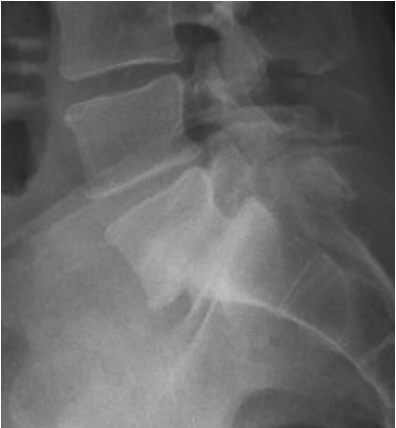

X-ray image of the lower spine showing a highlighted area with an arrow, with marked regions in red and green.